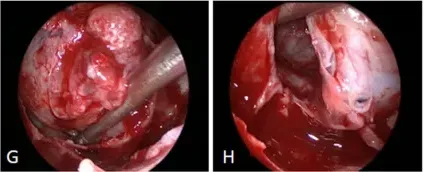

手术过程:由于视神经脑池段和视神经管段间明显粘粘扭结,所以先行经鼻内镜视交叉分离和固定保护(图3)。视神经管近端磨除骨质,然后切除残余肿瘤。使用人工硬脑膜关颅,水密缝合,防治脑脊液漏。通过横膈膜观察视蛛网膜池的视神经,并使用腹部脂肪向鞍内填充,使用鼻中隔骨和钛网重建鞍底。

图3:(e,f,g,h)显示前交通动脉复合体的鞍内疝(e),右侧视神经管钻孔骨质磨除(f),硬膜外剥离鞍内肿瘤(g),然后硬膜内切除肿瘤(h)。